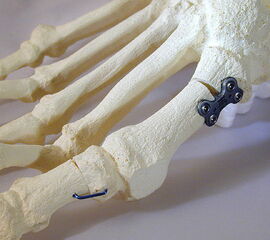

Abbildung 2

• Kleines Fußinstrumentarium.

• Herstellerspezifisches Plattensieb und Osteosynthesen für ergänzende Korrekturen (z.B. Axomed Pedus-O® (Abb. 2.) -Axomed GmbH, Heinrich-von-Stephan-Str. 5c, 79100 Freiburg; Darco MFS® - DARCO GmbH & Co. KG, Gewerbegebiet 18, D82339 Raisting; Merete® - Merete Medical GmbH, Alt-Lankwitz 102, 12247 Berlin usw.).